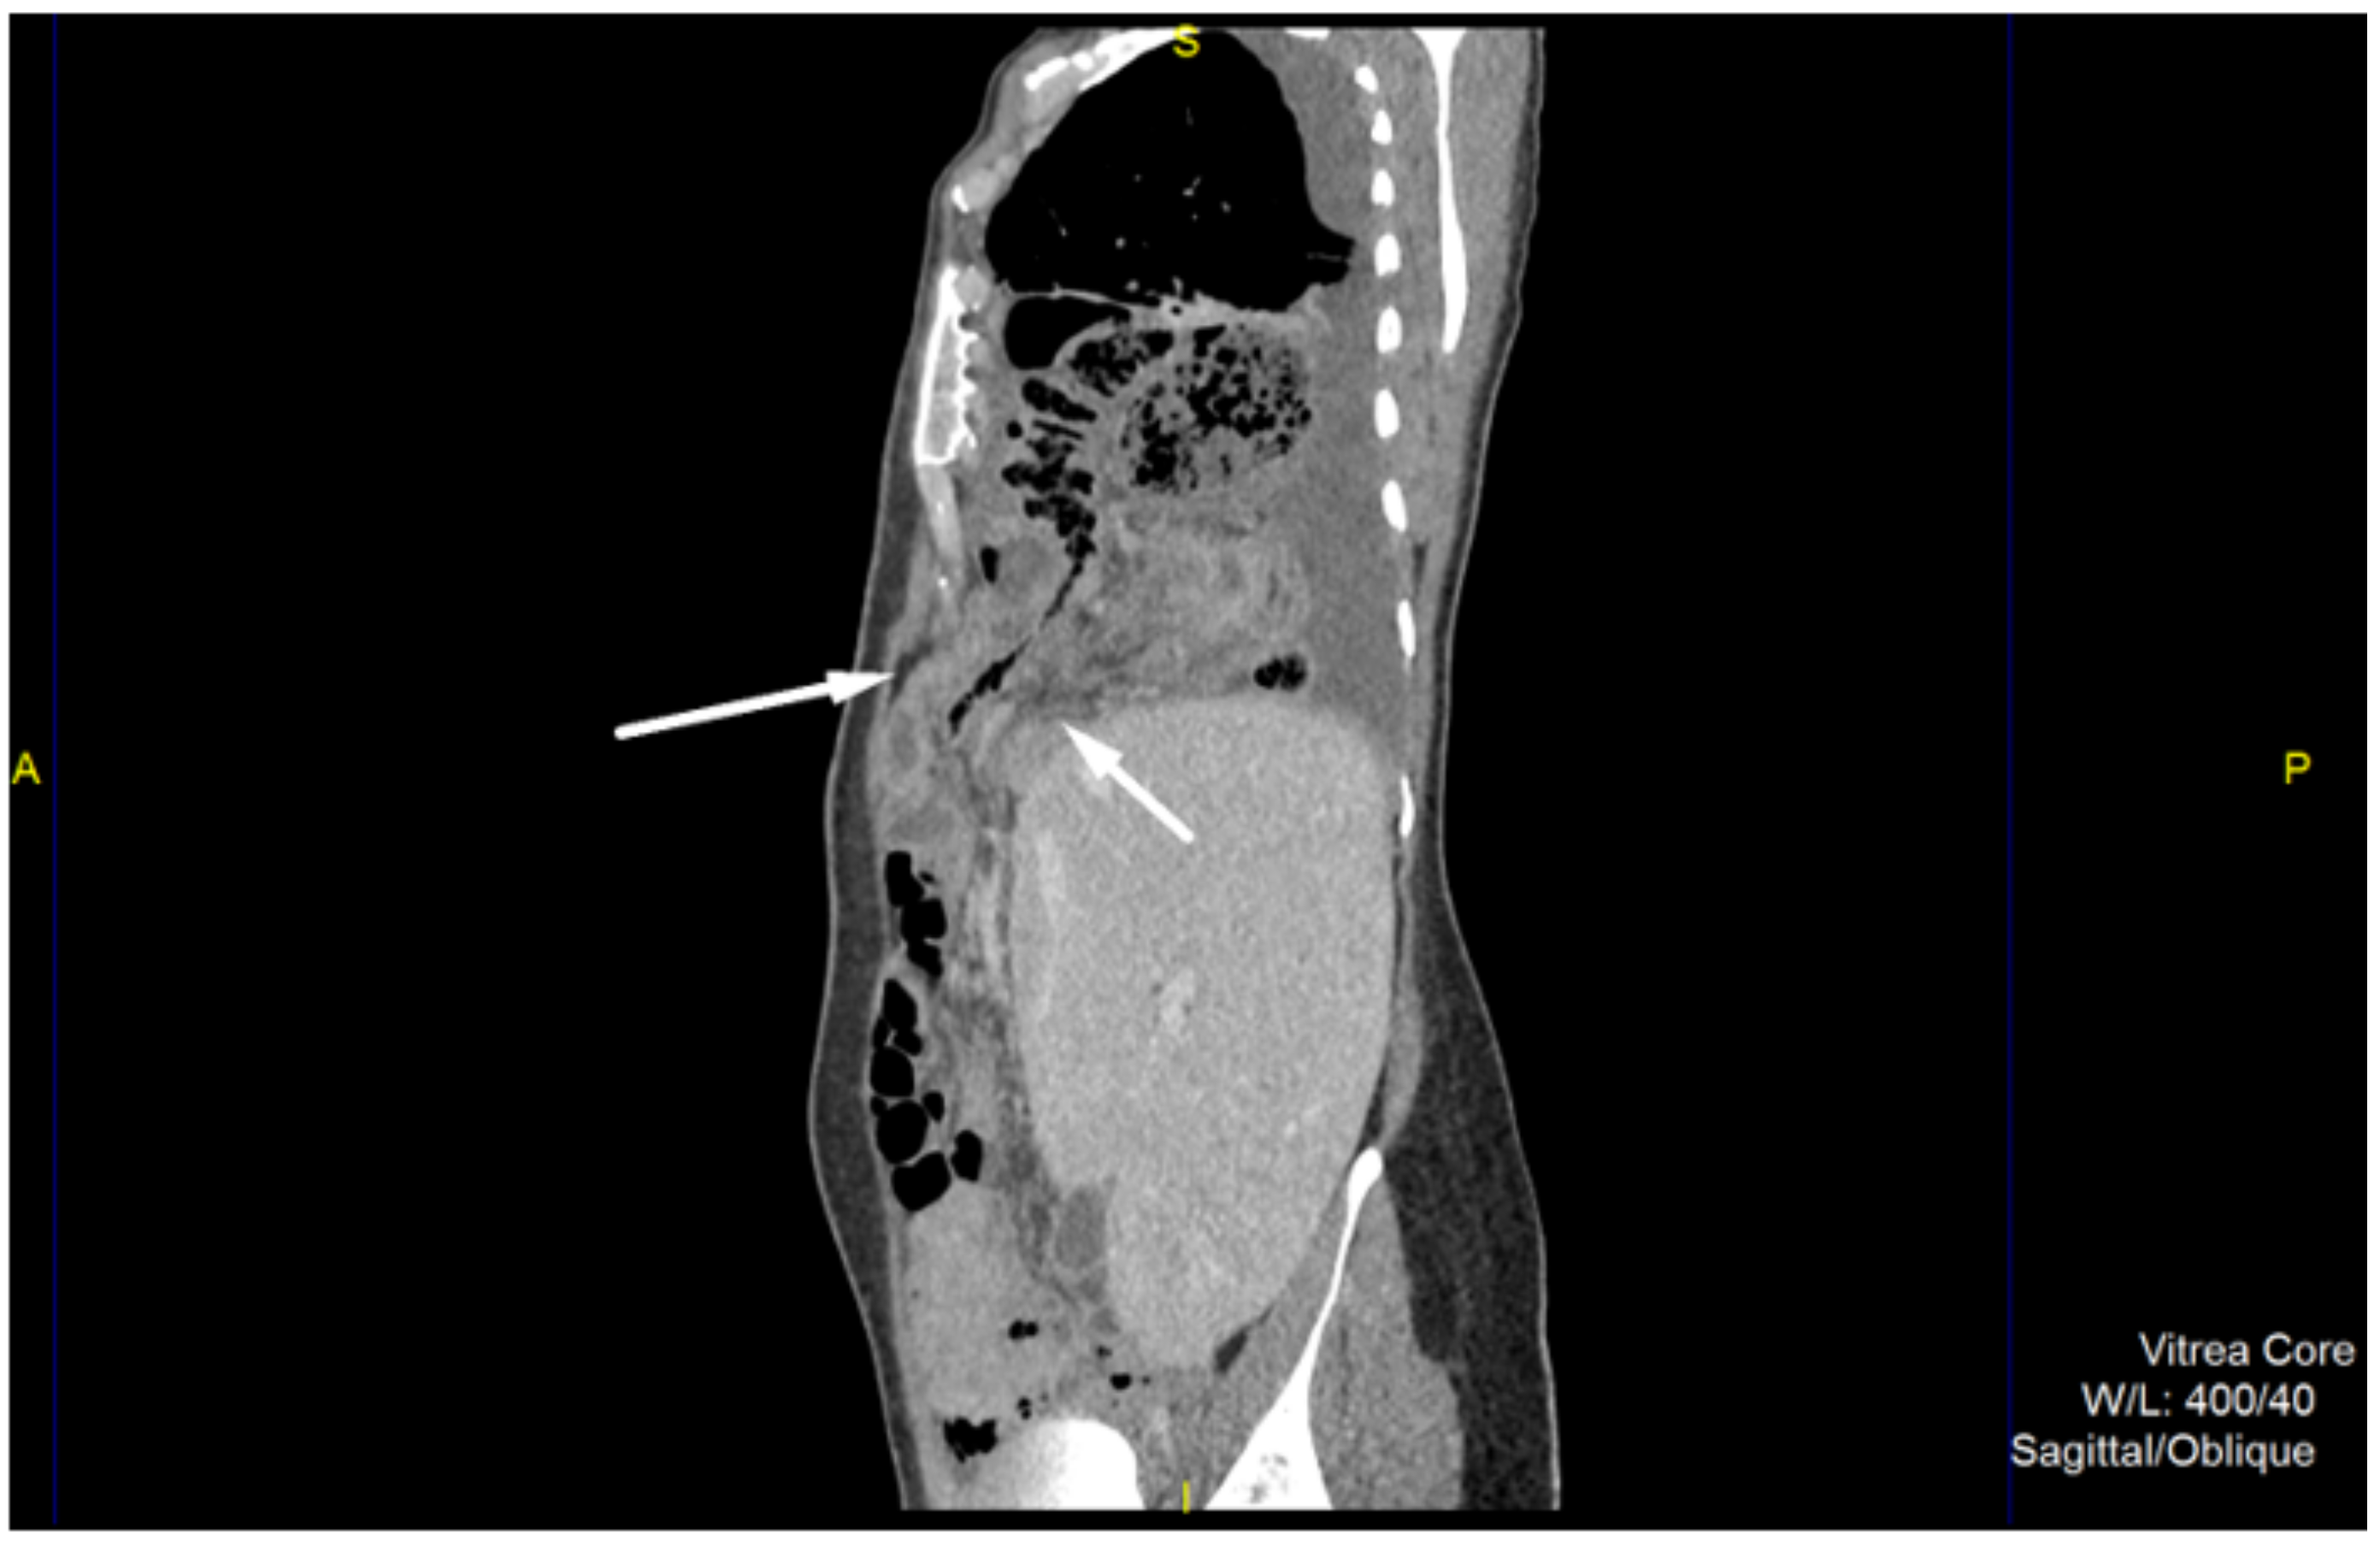

2. Case Report